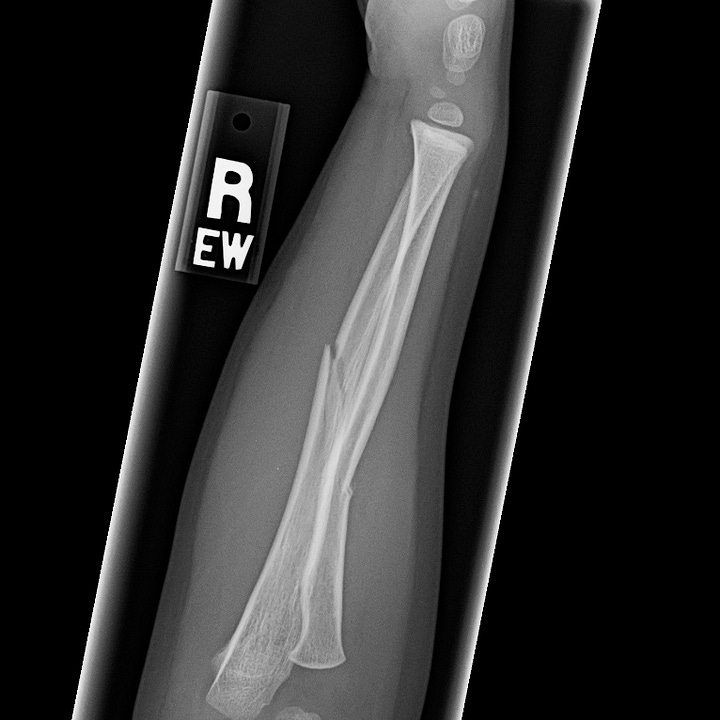

Greenstick fractures are incomplete fractures of long bones of children that result from forces perpendicular to the axis of the bone. Young children have more compliant long bones that have a greater tendency to bow and bend under stress rather than fracture. Greenstick fractures consist of a complete fracture or cortical disruption of the bone opposite the impacted side while the ipsilateral cortex remains intact. Treatment consists of closed reduction and immobilization.

Subtle greenstick fracture. The distal ulnar diaphysis is bowed toward the radius with subtle disruption of the radial aspect of the distal ulnar cortex.